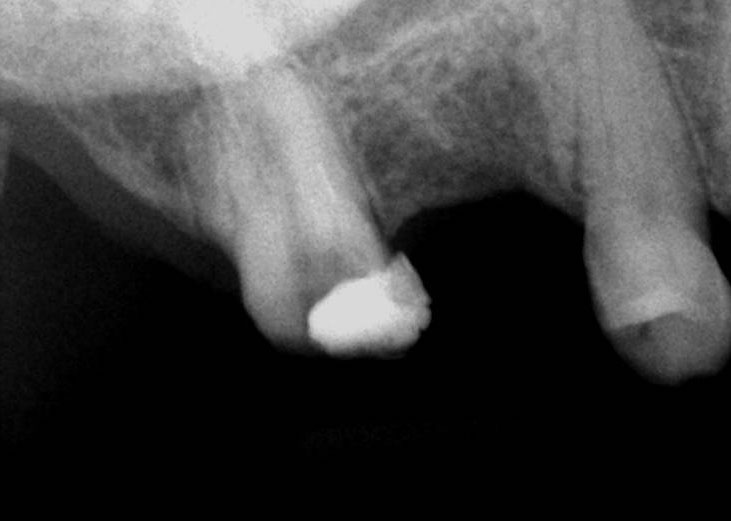

Pre-op

Canal Cleaned

Dens Tract Cleaned

Obturation + Fiber post + Composite core

Post-Obturation (Pre-Surgery)

Before root-end resection

After initial root-end resection. Apical “Pouch” still unexposed

Further root resection and cleaning of the “Pouch”

Apical pouch filled with MTA

Post-Op

Pre-op & Post-op